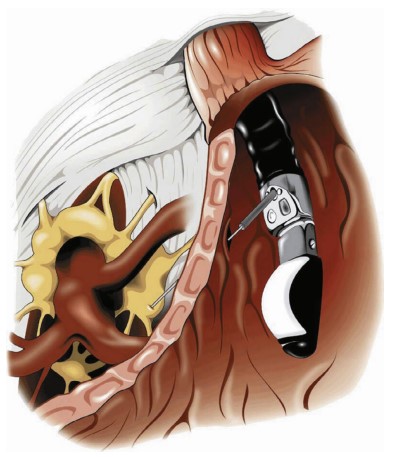

Endoscopic Ultrasonography (EUS)-guided ablative therapy represents a significant advancement in the treatment of pancreatic diseases. This minimally invasive technique involves the injection of cytotoxic agents directly into cystic cavities or ganglia, aiming to eliminate premalignant epithelium or to achieve neurolysis. It offers a promising option for patients, potentially reducing the need for more invasive surgical interventions.

The celiac plexus block or neurolysis is the most common EUS-guided intervention in current practice, particularly for managing significant pain associated with pancreatic cancer. This procedure involves the injection of ethanol to achieve pain control, offering significant relief. For patients suffering from abdominal pain due to chronic pancreatitis, the results can be more modest, but still provide a crucial improvement in quality of life.